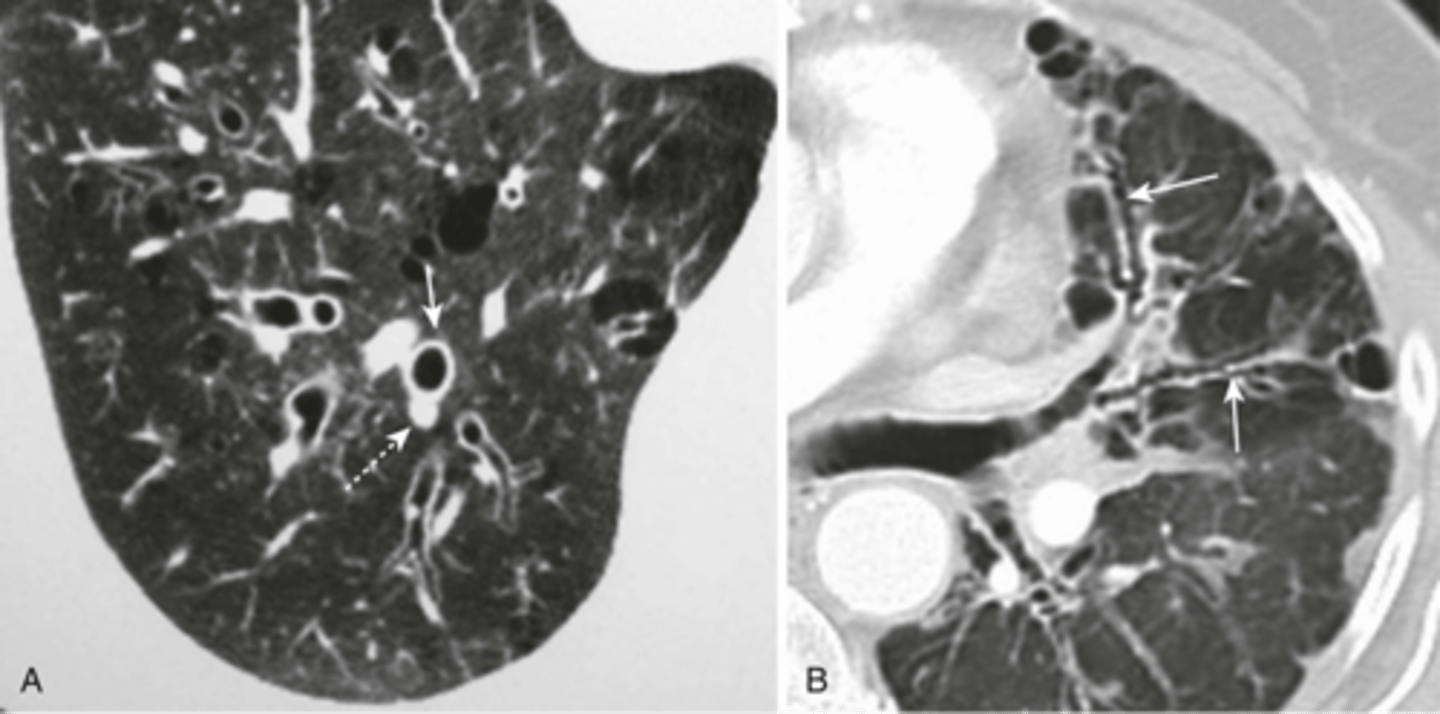

-MC at lung base, posteromedially and must be subpleural

-consequence of chronic pleural scarring (Asbestos, TB)

-will see rounded densitiy at lung bse, comet tail, and crow's feet

round atelectasis on a CT